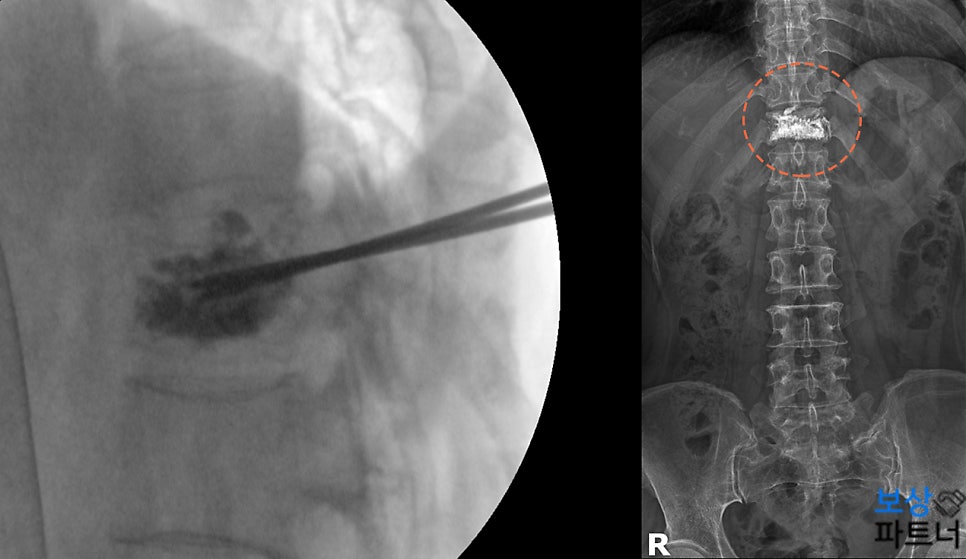

경피적 추체성형술 (골시멘트술) 정밀 검사 결과, 흉추 11번 부위가 압박골절되었다는 소견이 나왔으며 X-ray 방사선 검사와 MRI 영상을 보면, 해당 척추체의 높이가 감소한 모습을 확인할 수 있습니다.

이어서 골밀도 검사 결과는 심한 골감소증으로 나왔는데요. (골다공증 직전의 상태) 뼈가 많이 약해진 상태라고 판단한 주치의는 골시멘트를 주입하여 뼈를 굳히는 '경피적 추체성형술'(Kyphoplasty)을 권하였습니다.

의료용 시멘트를 주입하여 빠르게 굳히는 이 방법은. 당일 퇴원도 가능할 정도로 회복 속도가 빠른 것이 특징입니다. 통증을 경감시켜주고 추가적인 척추의 붕괴도 막아주기 때문에, 뼈가 약한 분들에게 주로 이러한 시멘트술을 시행하게 됩니다.